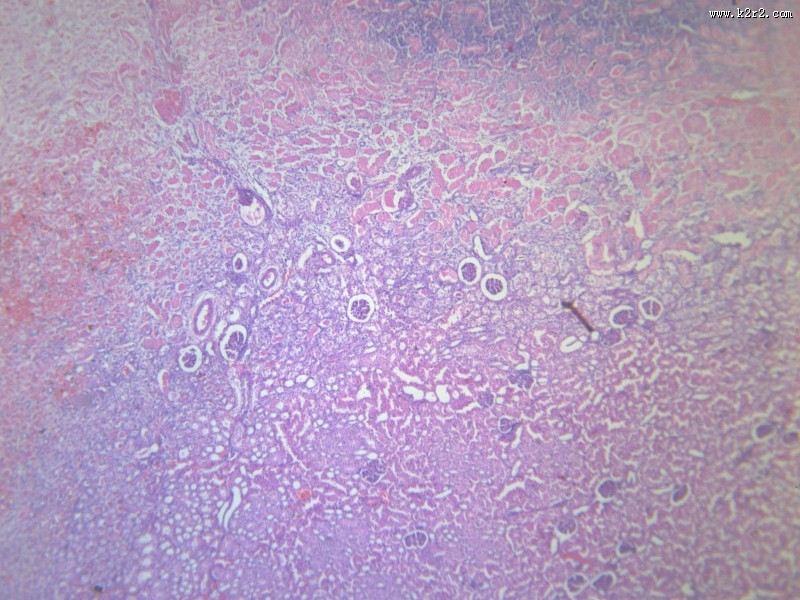

肾凝固性坏死 - 第3张

肾凝固性坏死

kidney coagulative necrosis